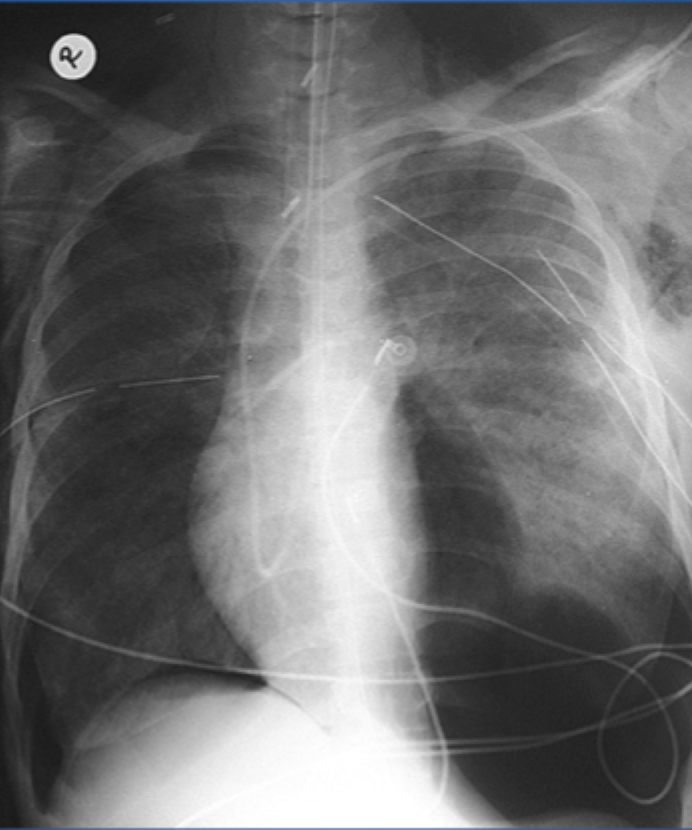

Tension pneumothorax:

-Large amount of air in the affected hemithorax and CONTRALATERAL shift of the mediastinum